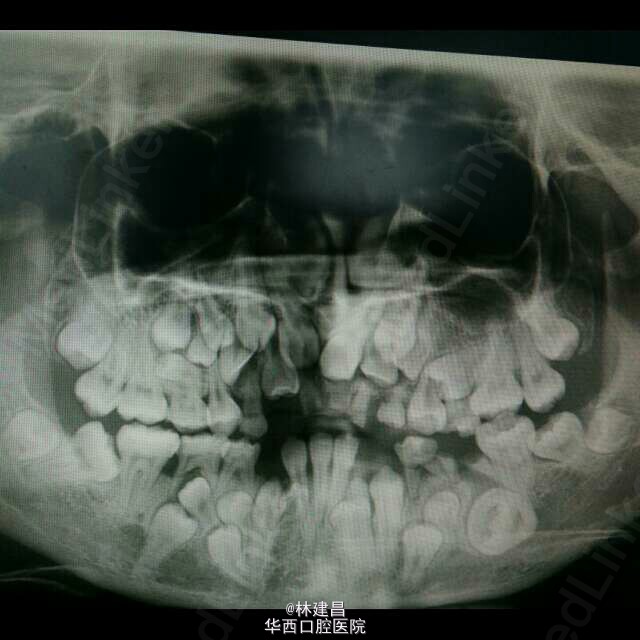

讨论:颅骨锁骨发育不全(CCD)综合征是一种罕见的先天性遗传性疾病,多为常染色体显性遗传。发病率约1/100万,2/3有家族史,男女发病无明显差异,可在任何年龄发病。CCD病变可累及人体所有骨骼,以骨缺如和膜性化骨发育障碍为特征。多数患者的临床特征在成年后才表现出来,因此幼年时难以诊断。患儿在儿童期如有骨骼发育不良的表现,应与佝偻病、早呆症、成骨不全、软骨发育不全、致密性成骨不全等鉴别。CCD综合征无特殊治疗,如有血管神经卡压症状可进行矫形减压治疗;面部畸形也可进行相应正畸治疗。本例患儿因有严重的颅骨锁骨缺如及骨骼典型x线表现,虽无以上典型临床表现及染色体检查,但结合家族有连续四代直系亲属结婚史及家族中普遍身材矮小,新生儿期可早期诊断。如临床有颅骨缺损及全身骨发育不良的病例,在考虑此综合征时,应对其家族成员进行家系调查及染色体检测。同时应加强产前检查,做好新生儿健康筛查,保证优生优育。